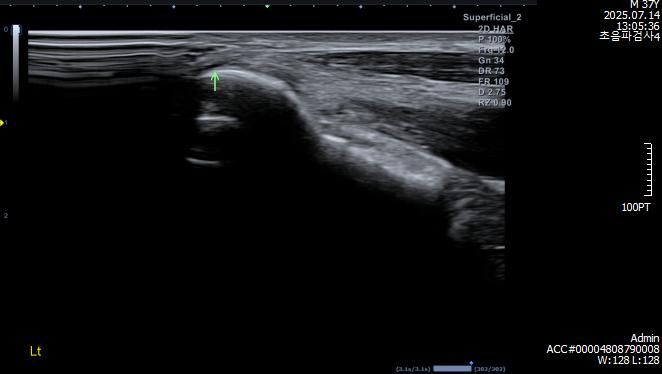

검사 결과 (7월 중순)

- MRI: 좌측 삼두건 경미한 염증, ulnar nerve supracondylar level 경미한 신호 증가

- 초음파/근전도: 척골신경 아탈구 확인

아래는 관련 사진 첨부합니다.

• 4번 째 사진